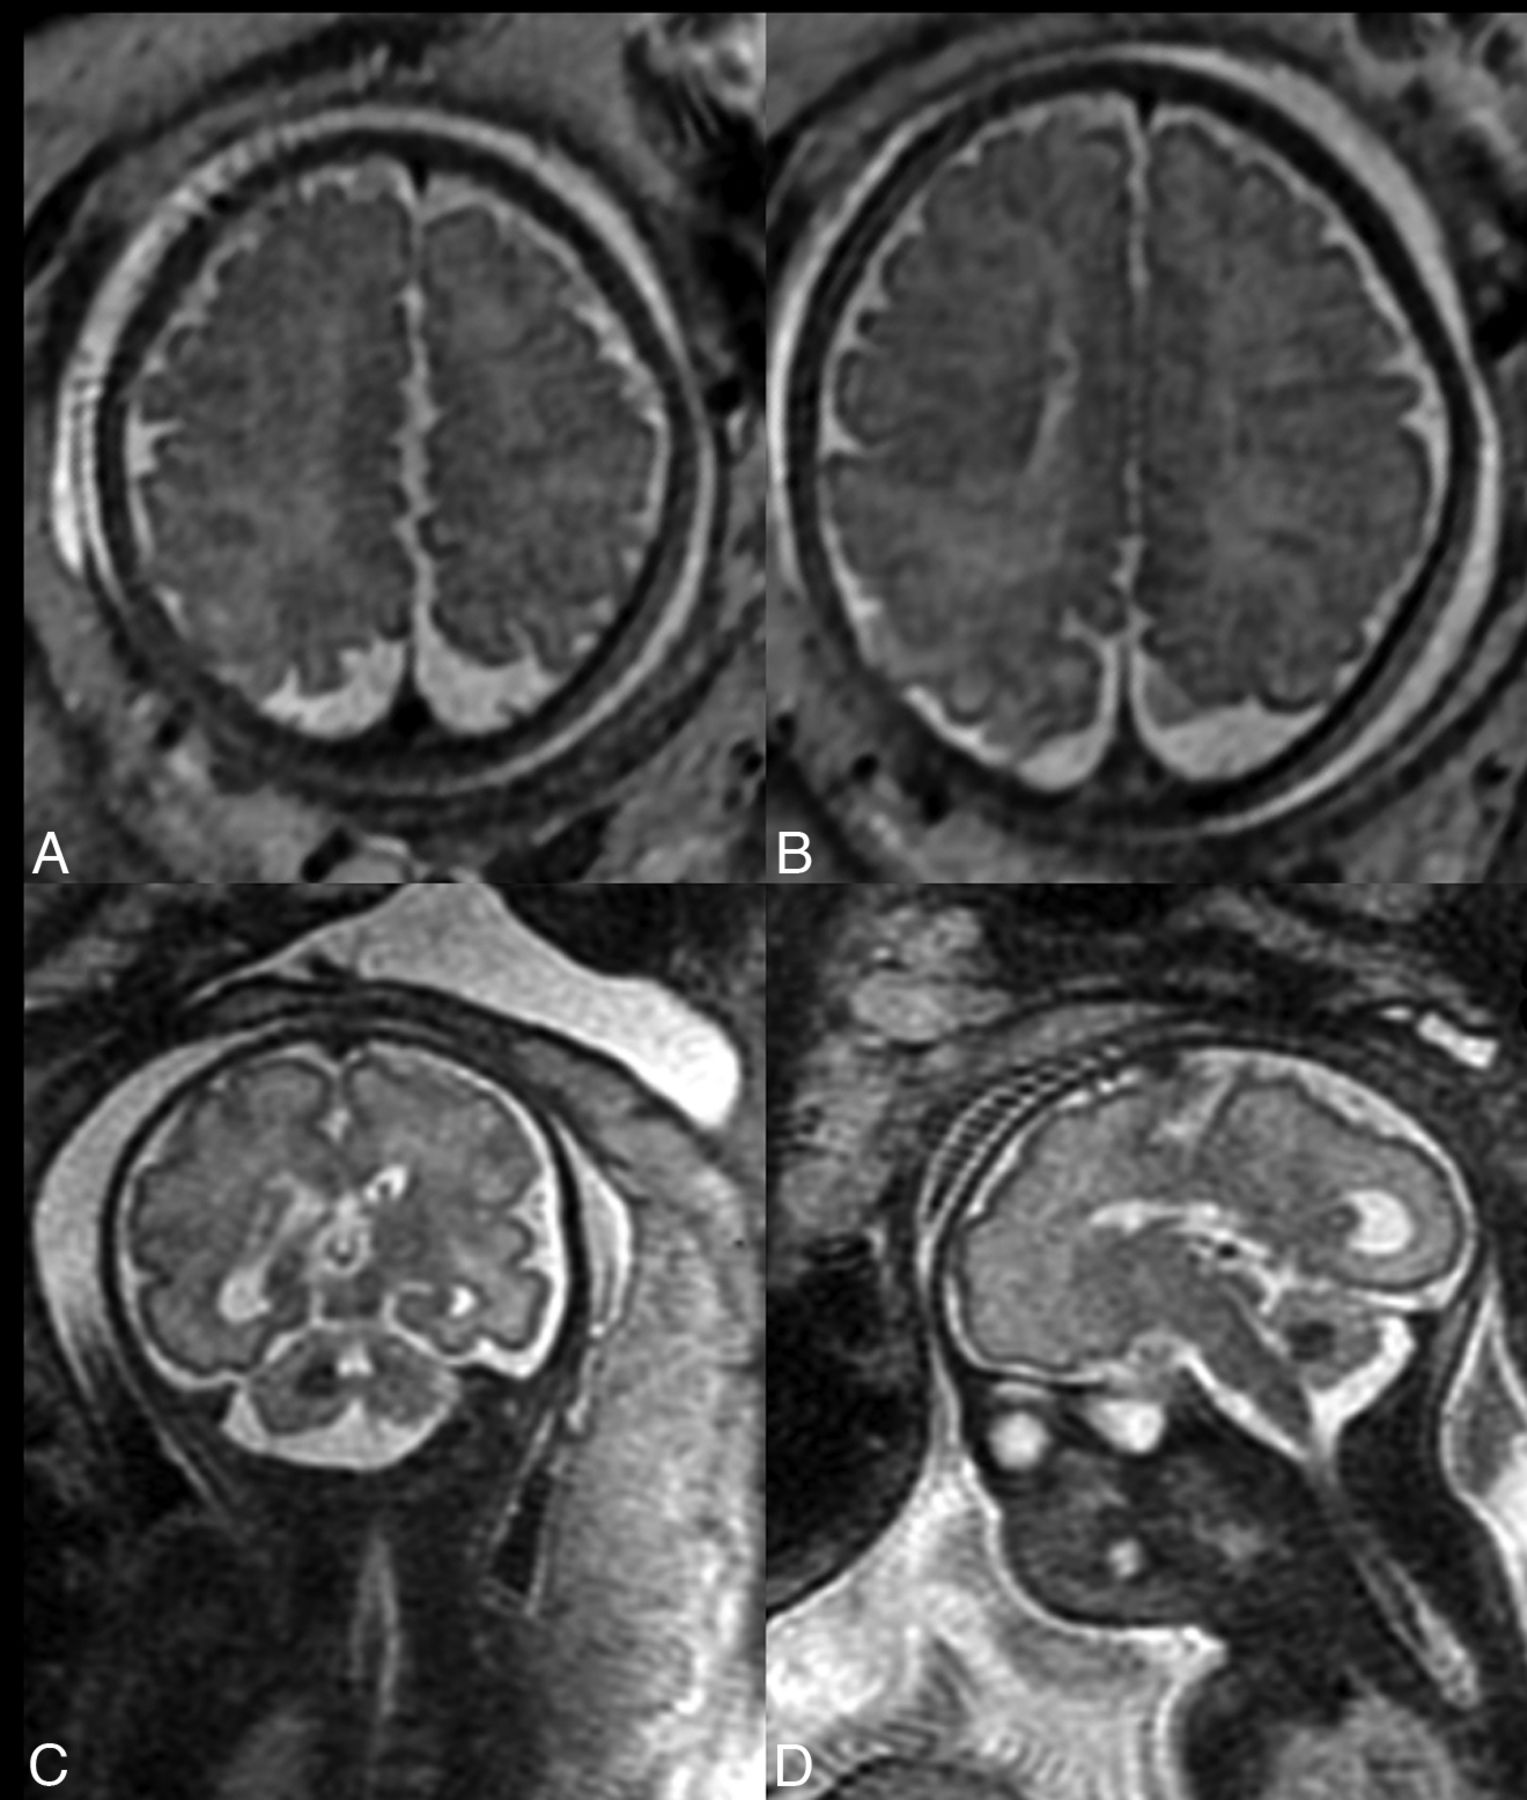

SENs are occult to US and are detected only on MR imaging in most cases. These nodules are T2-hypointense (Fig 2) and, according to the literature, display typically bright signal on T1-weighted images.12,13 The latter was not obvious in our experience, most likely due to the suboptimal quality of T1WI and the small size of these nodules. SENs should not be diagnosed unless they are demonstrated in 2 different projections, eg, axial and coronal, to avoid misdiagnoses. The differential diagnosis of SENs on fetal MR imaging includes subependymal heterotopia and subependymal hemorrhage.12 Nagaraj et al14 added to this list abnormal nodularity of the germinal matrix that does not correspond to subependymal heterotopia postnatally. The normal germinal matrix that forms on the ventricular walls is smooth and symmetric. During development in utero, it increases in volume between 13 and 26 GWs, then loses half of its volume between 26 and 28 GWs, and decreases further thereafter. Between 26 and 28 GWs, the germinal matrix is at high risk of hemorrhage.13 However, subependymal hemorrhage is often associated with ventricular bleeding, detected on US, and has a typical evolution on follow-up US.12 The nodular appearance of the ventricular walls that is depicted on MR imaging early in pregnancy, eg, at 21 GWs, suggests subependymal heterotopia; late appearance in the third trimester is more suggestive of SENs in TSC. In our study group, SENs were detected on prenatal MR imaging in 78% of cases in all fetuses with prenatally diagnosed TSC and represented the second major criterion in all cases of TSC. They were not described on US in any fetus in our study group.

T2-hypointense subependymal nodules on the axial (A), coronal (B), and sagittal (C) planes.